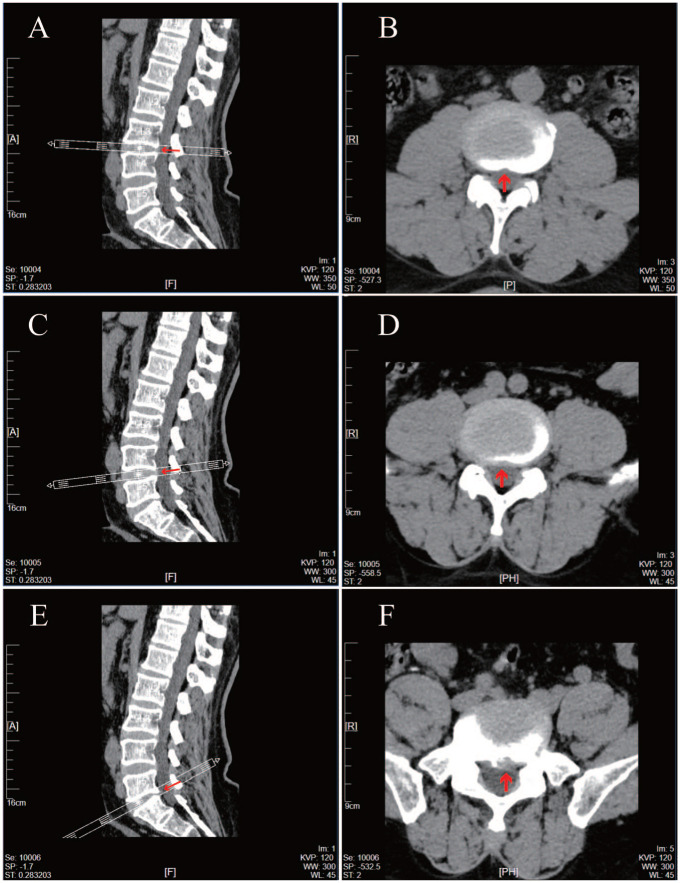

Chronic prostatitis/chronic pelvic pain syndrome (CP/CPPS) is a complex condition characterized by heterogeneous symptoms and unclear pathogenesis, often posing diagnostic and therapeutic challenges. Lumbar disk herniation (LDH) may compress the dural sac and irritate the cauda equina, producing subclinical symptoms that overlap with those of CP/CPPS and increasing the likelihood of misdiagnosis. We report the case of a 61-year-old man with an 8-year history of CP/CPPS unresponsive to standard treatments, including phytotherapy, anti-inflammatory agents, and physical therapy. Further evaluation revealed lower-limb weakness and low-back pain; lumbar CT identified disk herniation with dural sac compression. Treatment was revised to include traditional Chinese medicine (Mai Xue Kang capsules and a modified Chaihu-Guizhi-Ganjiang Decoction) along with lifestyle modifications, resulting in significant symptom relief and no recurrence at 6-week follow-up. A review of the literature supports the potential for LDH to mimic CP/CPPS symptoms, highlighting a diagnostic blind spot. This case emphasizes the importance of considering spinal etiologies in refractory CP/CPPS and advocates for a broadened diagnostic framework to enable more personalized treatment strategies.